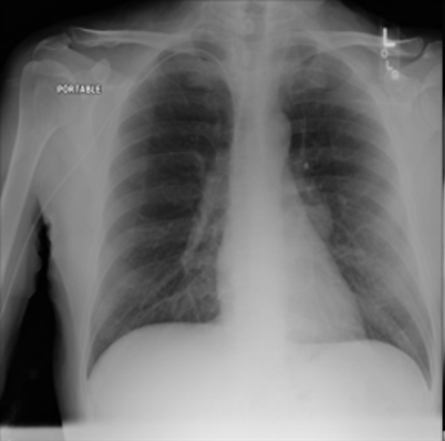

As an instance of this, the trained model was prompted in the generative setting for “carcinoma" in relation to a healthy image. The result is shown in Figure 4 alongside the real healthy scan and a separate real-case carcinoma. It is clear that the induced disease is visually comparable to that of the real case despite it’s absence from the training set. We propose that this capability arises as a result of a the internal correlation of the domain-adapted text encoder to that of the visual domain via the visual model, given that the domain-adapted text encoder is trained on the full panoply of Radiology reports.

To evaluate this in more detail we examine a less localised condition: Cardiomegaly.

Zero-shot evaluation: Cardiomegaly

The disease cardiomegaly (enlargement of the heart) was not present in the training data; to evaluate zero shot induction in this context, we take real images from the small version of the Chexpert[52] dataset (from https://www.kaggle.com/datasets/ashery/chexpert). Thus, 8060 images of positively identified cases of cardiomegaly were used as the reference image set for real cardiomegaly. Correspondingly, for each of the healthy images from the COVID 19 database, an induced version was generated by the model with the prompt “Cardiomegaly". FID scores between the real cases of cardiomegaly from the Chexpert dataset and the generated images are given in Table 4.

The FID scores in Table 4 indicate that the generated cardiomegaly images do not have a large distance (using the 275.0 baseline of the Roentgen[30] study) from the real images from which they were generated, suggesting appropriate perturbations were made and the generations were reasonably close to the real cardiomegaly set from the Chexpert dataset.

Interestingly, while generation across different settings of the visual diffusion hyperparameters Strength & Guidance-scale did not have a very significant difference on FID scores evaluated across the full range of image sets, visual differences for individual images could be more significant, as highlighted in Figure 5 for two different settings of the respective hyperparameters. This is presumably due to the different aspects specific to individual patient image (such as the prior health of the patient, structural variances due to age, recording equipment, size etc) acting to mimic hyperparametric variation, which primarily appears to affect the opacity of the induced material for hyperparameter settings ranges consistent with good image generation (in general, the Strength hyperparameter give scope for larger perturbation from the original image during diffusion, while Guidance-scale determines the intensity of text prompt conditioning; optimal settings of these parameters are inherently disease-specific given the wide variation in the amount of pixel opacity needing to be added in the disease induction setting of the pipeline).